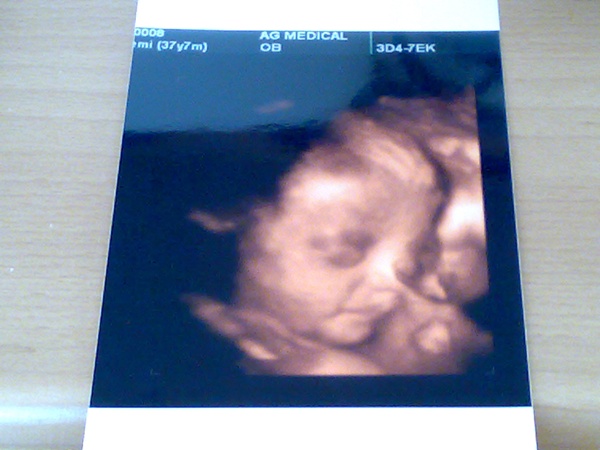

Mia, örülök, hogy minden rendben volt a dokinál! Jajjjj, olyan jó amikor mocorog!!!! És az milyen jó lesz mikor kivülről látjátok majd, hogy épp kidugta, a sarkát!!!!! Én annyira imádtam!

Milyen tündérmanó a pici lánykád! Nagyon szép! Mikor mi az első uh-on voltunk Lilivel, olyan kis formás paca volt, hogy mondtam, tuti lány lesz....